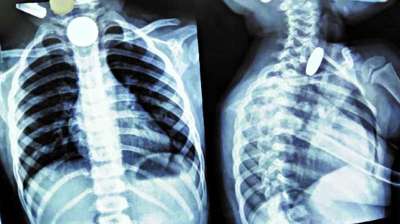

खिलौना नहीं सिक्का था! बच्चे ने निगले 5-10 रुपये के सिक्के, डॉक्टरों ने ऑपरेशन कर निकाले

24 Jul, 2025 04:09 PM IST | SATYAEXPRESS.COM

दिल्ली : दिल्ली के एक सरकारी अस्पताल के डॉक्टरों ने 12 वर्षीय बच्चे की जान बचाई है। बच्चे ने पांच और दस रुपये के तीन सिक्के निगल लिए थे। सिक्के...